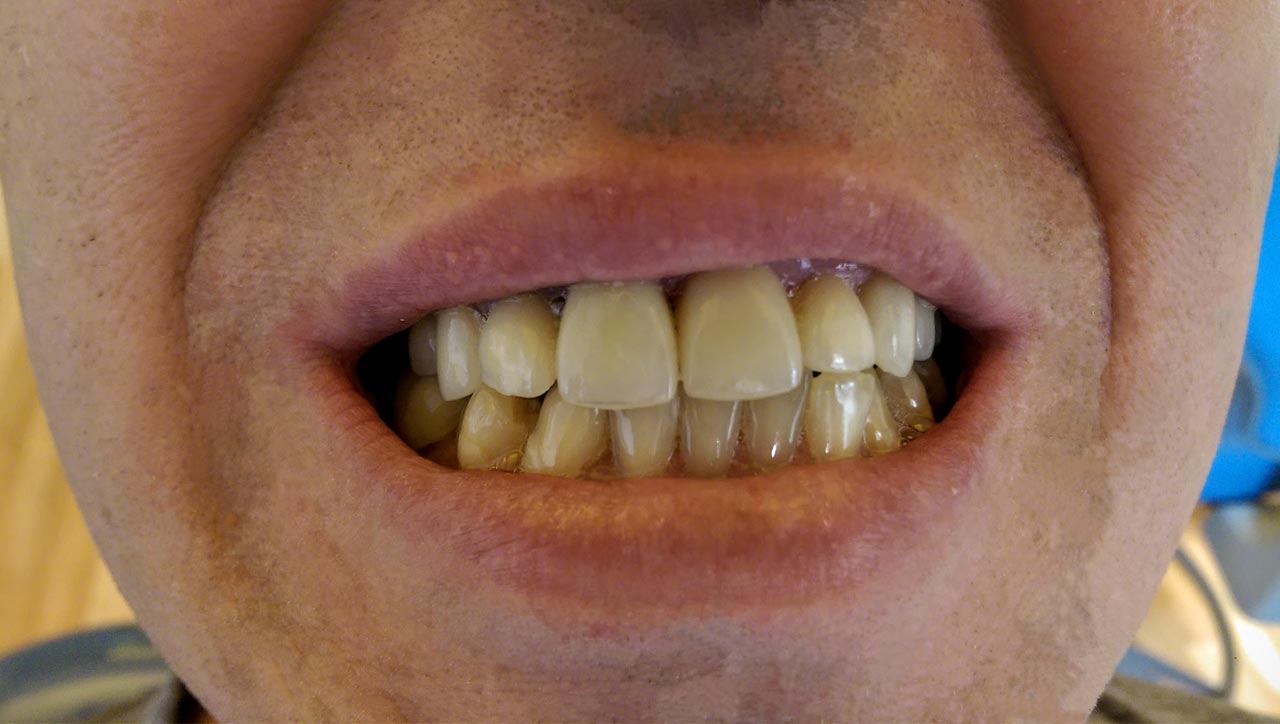

Elhanyagolt fogsor cseréje 2 nap alatt

2 nap alatt varázsoltuk ezt a szép esztétikus alsó, felső körhídat implantátumokkal megtámasztva a korábban elhanyagolt szájba. Az 1. nap 26 fogat távolítottunk el, mert annyira rossz állapotban voltak, és rögtön azonnal terhelhető IHDE svájci implantátumokat raktunk be, fentre 8, lentre 6 darabot. A sebeket összevarrtuk és intraorális szkennerrel digitális lenyomatot vettünk. 2 nap múlva pedig beragasztottuk a kész PMMA műanyag körhidakat. Dr. Kelemen Péter és a Symbion Fogtechnika munkája.